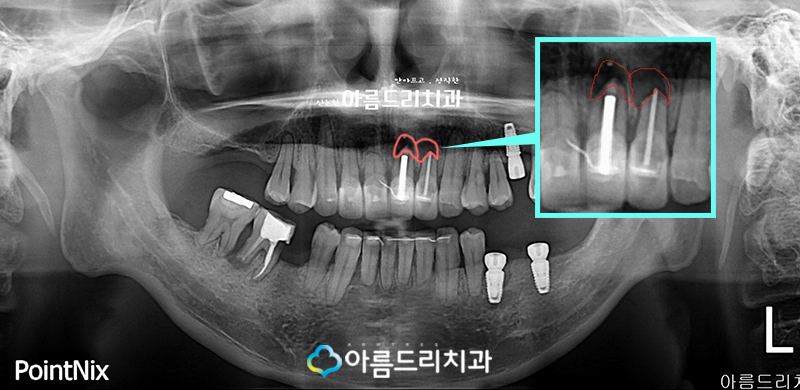

환자분의 사진을 보면 전치부 상악의 윗부분 표시한 부분에서 확대한

사진을 보시게 되면 검게 보여지는 부분을 확인해 보실 수 있는데요.

이건 치아 뿌리쪽 염증이 심하다는 것을 의미하며 조치가 필요한 상황입니다.